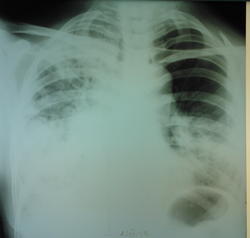

+1. А слева отсевы в язычки.

С отсевом в "язычки" слева, как по мне, тоже не поспоришь.

В верхней доле слева не прослеживается легочной рисунок... Возникла мысль о пневмотораксе, не исключая вышесказанные диагнозы...

Как по мне, то этот "пневмоторакс" - технически-фотографический в большей степени, чем физический

ИМХО: все ставят на первое место казеоную пневмонию ( устаревшее название скоротечная чахотка).Но, при этом клиника отсутствует и верхушки лёгких с 2-х сторон отностельно чистые. Ещё с версией туберкулёза с обычным течением , когда могут отсутствовать жалобы, можно согласиться, но в вариант казозной (т.е. дестуктивной )ПНЕВМОНИИ , вериться с трудом.

Формально по рентгенограммам, особенно прямой, в первую очередь, на мой взгляд, можно подумать о гангрене правого лёгкого. Правда такой диагноз у многих вызывает неприятие.

сегодня пациентке провели контрольную R-графию (снимок только в прямой проекции и на другом аппарате - немного "мягче", предыдущий сломался, а этот боковой не смог снять), сравнить тяжело (на разных аппаратах, разная экспозиция и тд и тп) но по мне динамика отрицательная.